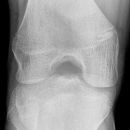

Tibiakopf 16 Jahre alt